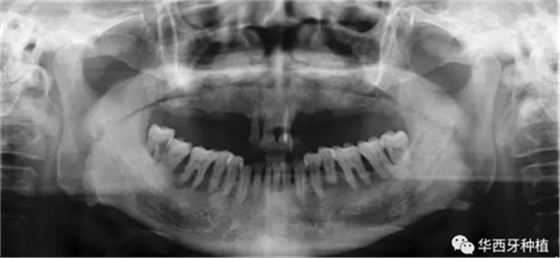

吳教授首先就全口牙缺失病種自身具有的特點,進行了總結。特別強調了嚴重的牙槽骨骨質萎縮,其結合上下頜骨的解剖結構(上頜竇,下齒槽神經管)后導致的種植區(qū)骨量不足。

吳教授提出:針對這些全口牙缺失的特點,醫(yī)生必須就選擇修復方式嚴格地管控適應癥。特別是普通的種植設計即以修復為導向的設計方式無法適用的情況。他的建議是:在回顧口腔種植技術的相關背景的同時,設計以骨條件為導向的有臨床針對性的的個性化的修復與手術方案。

接下來吳教授分別針對幾種具有不同特征的病例,進行分析、設計與病例回顧。對于不同骨量缺失的全口牙缺失患者,可選的種植修復方式有較為傳統(tǒng)的組牙種植修復、種植覆蓋義齒修復、all-on-four或all-on-six的修復方式。拓寬了我們在全口牙缺失病例種植與修復治療中的視野與選擇。

對于骨量較好的患者,選擇設計與手術方法較為簡單的傳統(tǒng)的組牙種植修復,過程較為便捷,遠期效果穩(wěn)定。但是時間與經濟成本高,并且在全口牙缺失患者口內,由于參照物較少,種植體的位置,共同就位與平行度的選擇與構建均存在一定難度。

對于骨質較差的患者,種植覆蓋義齒修復與all-on-four或all-on-six修復,則更為適合。

吳教授特別針對手術難度更大的all-on-four修復做了詳細的關于概念、設計、操作、修復的描述,首先是針對難度最大的手術環(huán)節(jié),就解剖、微創(chuàng)操作分別加以闡述。將他自己在臨床工作中的寶貴經驗分享給了大家。

對于傳統(tǒng)的all-on-four術式,吳教授加入了微創(chuàng)的指導思想,設計時同樣加入數字化三維重建與修復一體化設計,增加了手術的可控性,同時極大減輕了患者的創(chuàng)傷程度,縮短了修復周期。